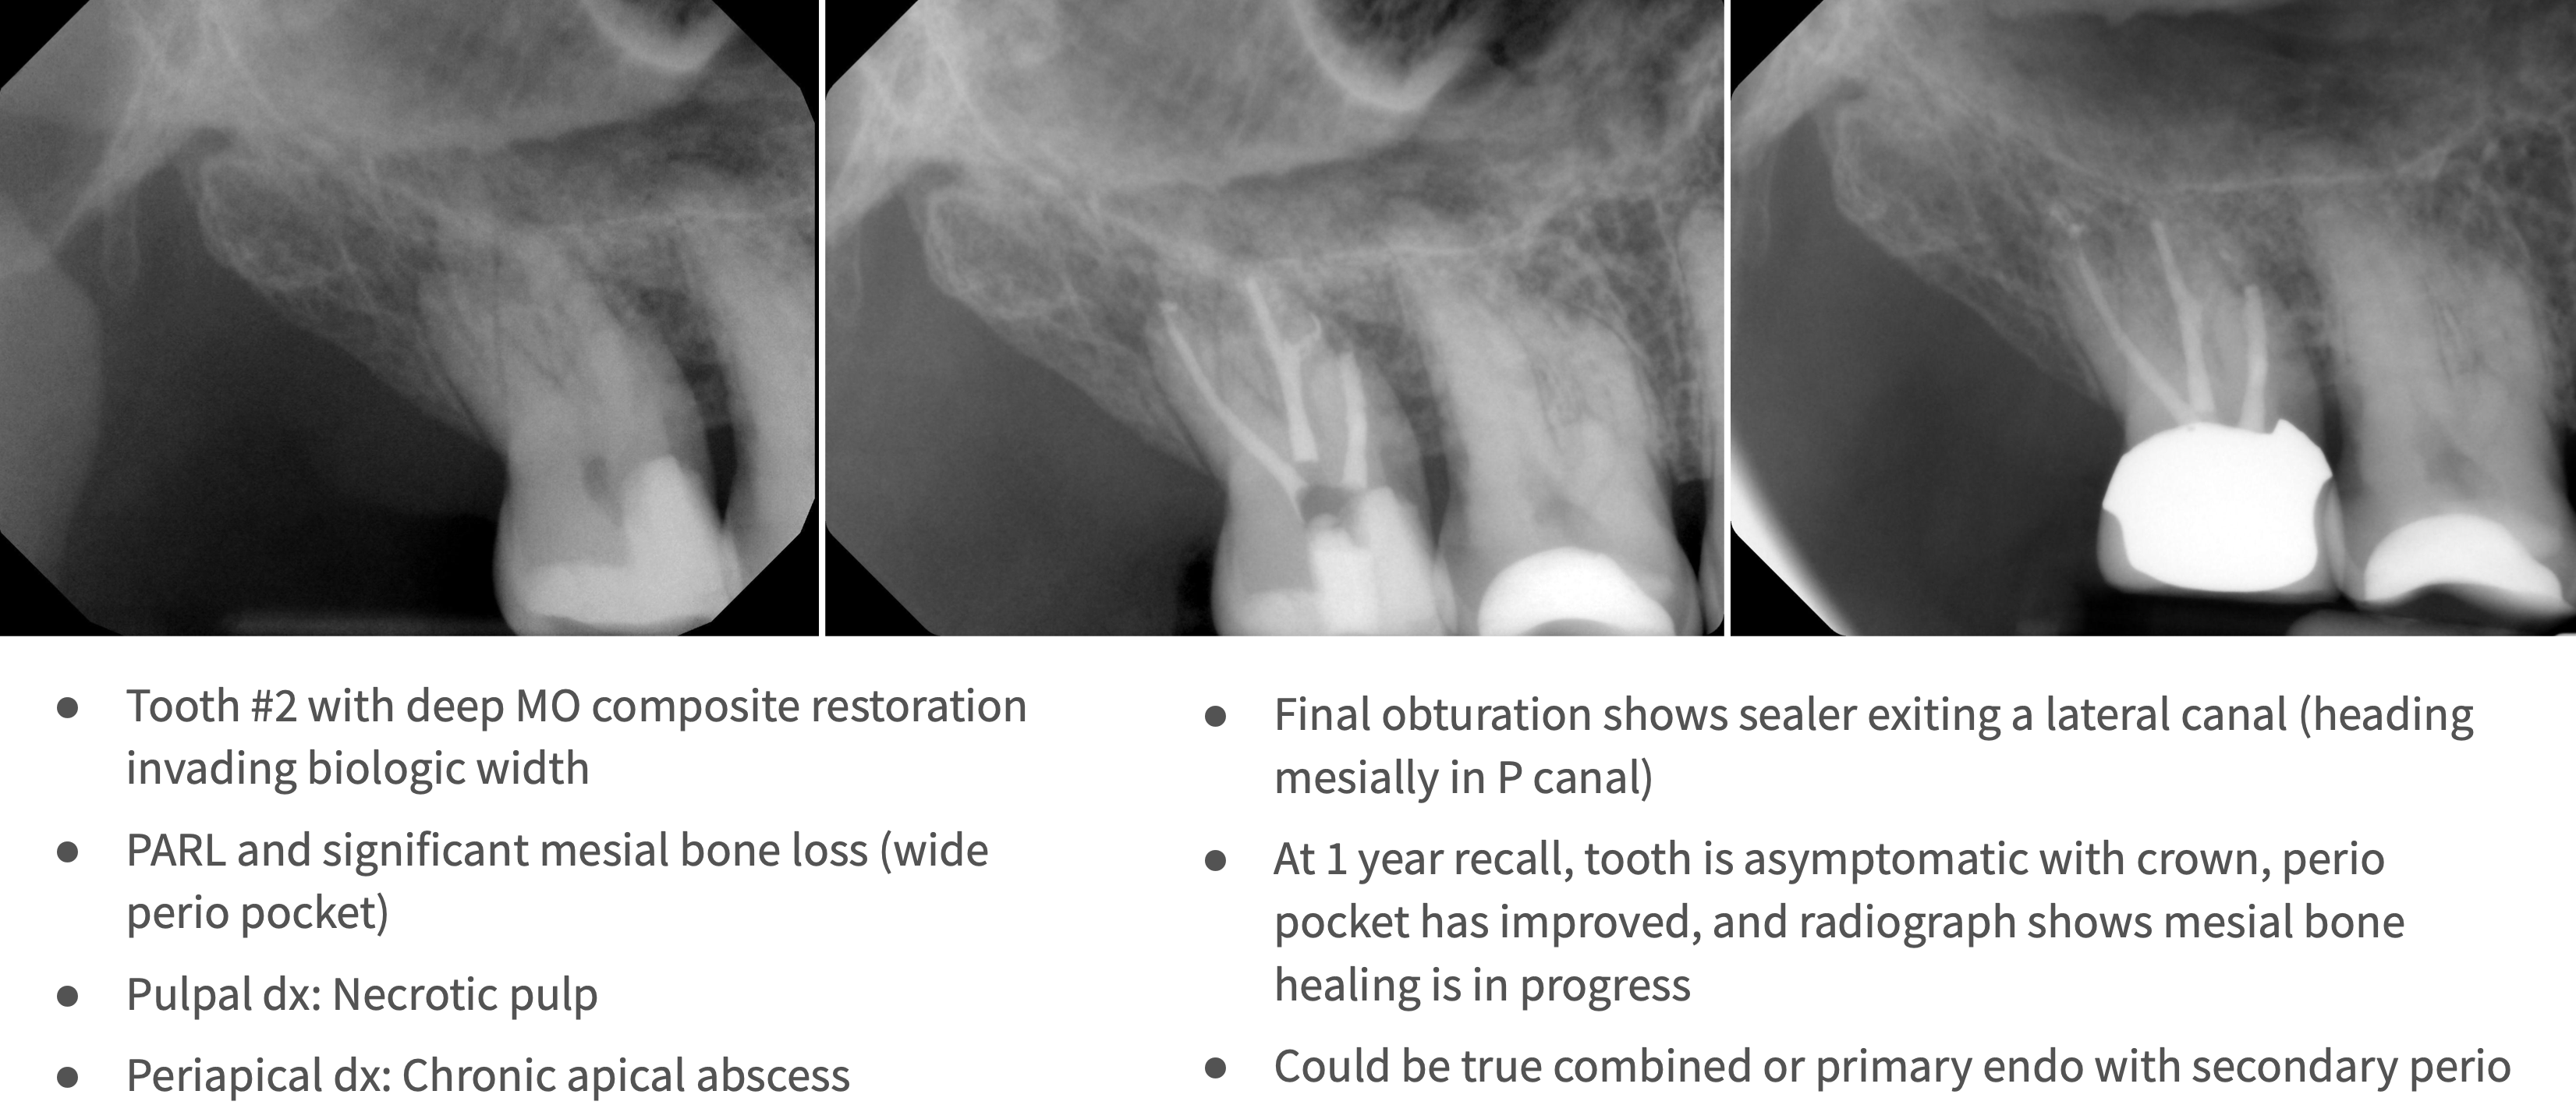

What type of lesion?

primary endo with secondary perio lesions

What is the pulpal diagnosis for primary endo with secondary perio lesions?

Necrosis (or Previously Treated)

What is the periapical diagnosis for primary endo with secondary perio lesions?

Chronic Apical Abscess

What is the treatment for primary endo with secondary perio lesions?

Non-surgical root canal treatment and final restoration

T/F: If perio was truly secondary in origin, any pockets and sinus tracts should resolve without any further periodontal treatment

True

When is the recommended follow up after RCT on primary endo, secondary perio lesion?

2-3 months to monitor gingival healing and to see if any additional treatment is needed

How long after RCT should bone heal on primary endo, secondary perio lesion?

1 year recall (but can take up to 5 years for resolution)

What does prognosis of on primary endo, secondary perio lesion depend on?

Endodontic treatment